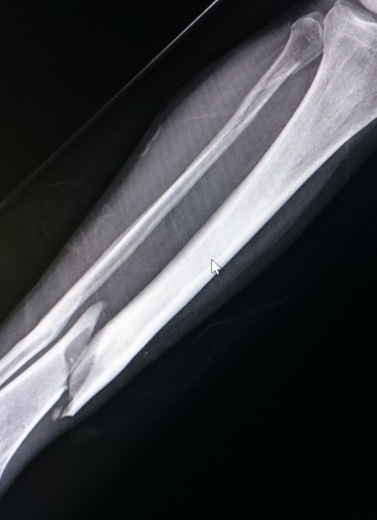

Bone fractures and trauma injuries need quick, accurate, and expert treatment to avoid long-term disability or improper healing. At our Fracture & Trauma Department, Dr. Anand Bhushan provides specialized care for all types of fractures — from simple to highly complex — using advanced surgical and minimally invasive techniques.

We Treat All Types of Bone Injuries and Trauma Cases

Complex & Comminuted Fractures